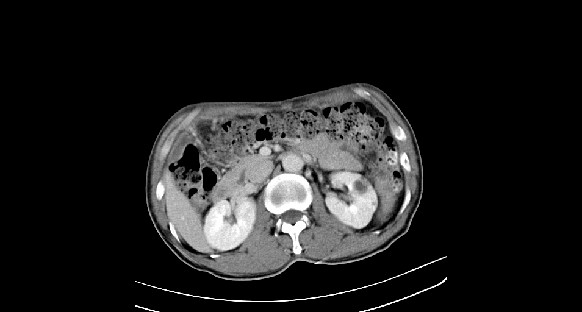

男性,70岁,体检b超发现左肾占位,请各位战友发表一下观点

左肾有两个病灶,且较大的病灶内可见点状钙化灶,增强扫描边缘也是呈渐进性强化,中央部分未见明显强化